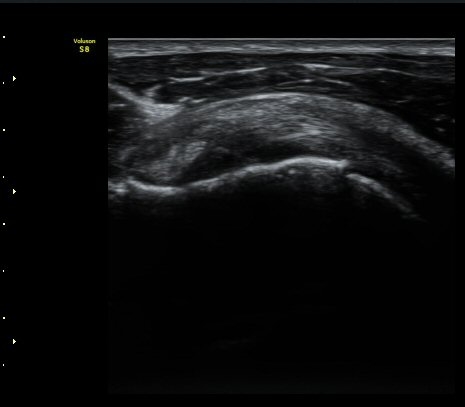

±Ø»ó°Ç ³»Ãø Á¾´Ü¸é°Ë»ç¿¡¼­ ƯÀÌ ¼Ò°ßÀ» º¸ÀÌÁö ¾ÊÀ¸³ª(»çÁø 4)

±Ø»ó°Ç ¿ÜÃø Á¾´Ü¸é°Ë»ç¿¡¼­ ±Ø»ó°Ç ºÎÂøºÎ Àú¿¡ÄÚ °á¼Õ°ú ´ë°áÀýÀÇ ºÒ±ÔÄ¢º¯È­°¡ °üÂûµÊ(»çÁø 5)